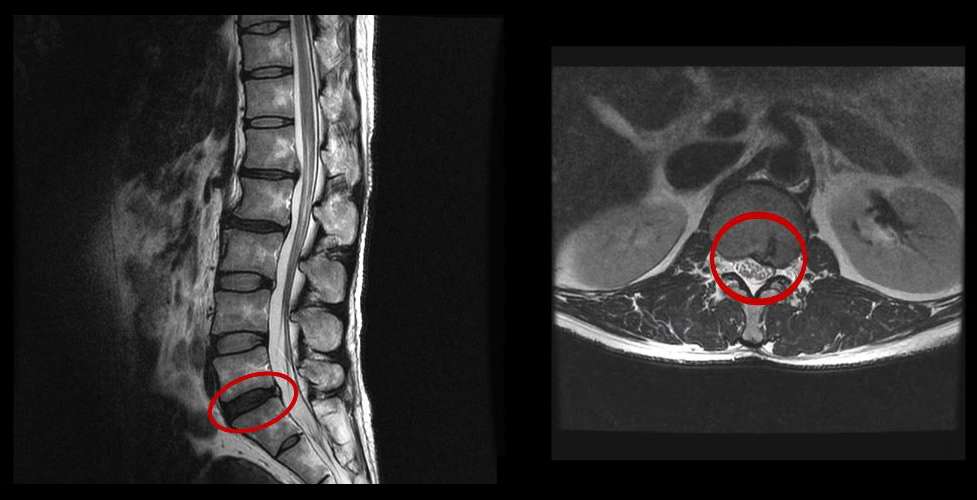

먼저 이 환자분의 치료 전 상태를 MRI와 함께 설명 드린 후 환자분의 얘기를 직접 들어보겠습니다.

그런데 이 환자분의 MRI를 보면 여러 마디에 퇴행성디스크가 있습니다.

이 환자분은 MRI상으로 거의 대부분 마디의 디스크가 퇴행되고 수핵이 밀려나와 있으며, 정상적인 허리 마디는 4-5번 하나 정도입니다. 그렇기 때문에 MRI만 보면 아마 대부분의 병원에서 허리디스크탈출 또는 퇴행성디스크로 인한 허리통증 및 다리통증으로 진단하고 치료할 것입니다. 이분도 그래서 20년간 그런 치료를 무수히 많이 받았으나 그 어떤 치료도 별 도움이 되지 않았습니다.

이 환자분처럼 오랜 기간 만성적인 허리통증이 있고, 엉덩이가 저리면서 심지어는 양쪽 다리저림까지 있는 환자분들이 많습니다. 그런데 이 환자분의 MRI를 보면 여러 마디의 퇴행성디스크, 디스크탈출, 황색인대의 두꺼워짐, 후관절의 퇴행 등 다양한 병변들을 가지고 있는 걸 볼 수 있는데요. 그렇기 때문에 많은 병원에서 이분을 디스크로 진단하고 거기에 따른 치료가 이루어졌습니다. 그러나 저희가 보기에는 이분의 MRI상으로 보이는 여러 마디의 디스크 문제가 이 환자분이 갖고 있는 증상을 설명할 수 없었습니다.